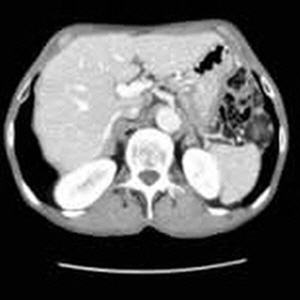

복부 CT 장비는 링 형태의 기계 내부에 방사선 투사 장치와 감지기가 내장되어 있습니다. 환자는 이 링 내부에 누워 있으며, 장비가 부드럽게 회전하면서 단면 이미지를 촬영합니다. 각각의 이미지들은 컴퓨터 소프트웨어에서 합쳐져 3차원의 고해상도 이미지를 생성하게 됩니다. 이러한 과정을 통해 의사는 대장, 간, 췌장, 신장 등 복부 각 장기의 상태를 면밀히 살펴볼 수 있습니다.

간은 인체에서 가장 큰 장기 중 하나로, 여러 가지 중요한 기능을 수행합니다. 간 질환은 매우 일반적인 문제로, 신속하고 정확한 진단이 필요합니다. 복부 CT를 통해 간의 경화, 종양, 지방간 등 다양한 문제를 확인할 수 있습니다. 특히 간암의 경우, CT 촬영은 초기 단계에서 종양의 크기와 위치를 평가하는 데 중요한 역할을 합니다. CT 이미지는 간 내 혈관과 주변 조직의 상태를 상세히 보여주기 때문에, 간암이 다른 장기로 전이되었는지 파악하는 데도 유용합니다.

신장은 인체의 대사 노폐물을 제거하고 수분 및 전해질 균형을 유지하는 중요한 역할을 합니다. 신장에 문제가 발생하면 체내의 여러 기능이 부정적인 영향을 받을 수 있습니다. 복부 CT는 신장 결석, 신장 종양 및 기타 신장 관련 질환을 진단하는 데 도움을 줍니다.